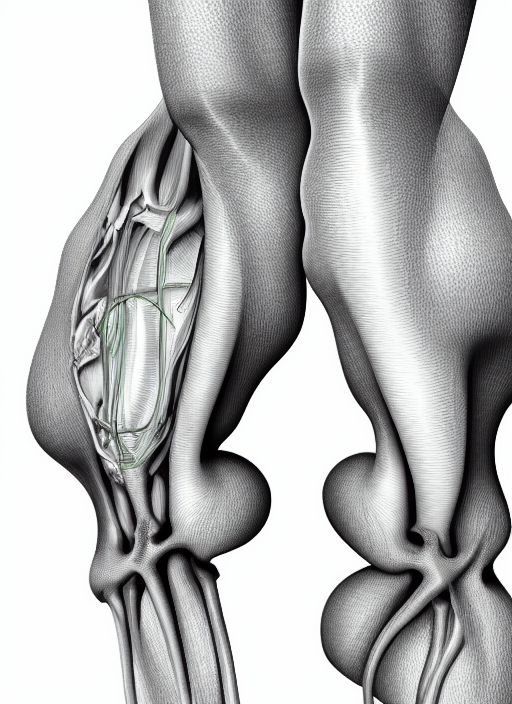

human bone, knee, human knee, knee, 3d rendered knee illustration, pain illustration knee side, 3d illustration knee side, Knee x-ray

anatomy and arthrosis biology blue body bone cartilage computer digitally dimensional dissection education femur file forensic generated graphic healthcare healthy human illness illustration image injury inside isolated joint knee leg lifestyle ligament loop-ready medical medicine meniscus morphology of osteoporosis painting patella people physical physiology render research rheumatism science shape skeleton surgery the three three-dimensional tibia transparent vertical visualization x-ray-

- Category Science